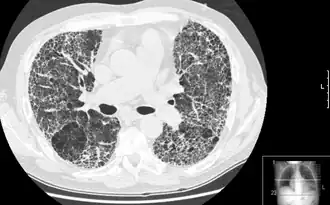

Imagen por tomografía computarizada de tórax en alta resolución mostrando un alto grado de fibrosis en parénquima pulmonar. | ||

La evaluación radiológica mediante TCAR es un elemento esencial en la ruta diagnóstica de la FPI. La TCAR se lleva a cabo con una gammacámara tomográfica axial computarizada convencional sin la inyección de agentes de contraste. Los cortes de evaluación son muy finos (1–2 mm).

La TCAR típica del tórax en un paciente con FPI muestra los cambios fibróticos en ambos pulmones, con una predilección por las bases pulmonares y la periferia.De acuerdo con las directrices conjuntas ATS/ERS/JRS/ALAT de 2011, la TCAR es un componente esencial en la ruta de diagnóstico de la FPI, la cual puede identificar NIU por la presencia de:[1]

- Opacidades reticulares, a menudo asociadas con bronquiectasia por tracción

- Panalización manifestada como espacios quísticos agrupados, normalmente con diámetros de entre 3 y 10 mm, pero a veces de mayor tamaño. Normalmente subpleurales y que se caracterizan por paredes bien definidas y dispuestas en, al menos dos líneas. Generalmente, una línea de quiste no es suficiente para definir la panalización

- Las opacidades con aspecto de vidrio deslustrado son comunes pero menos amplias que la reticulación

- Distribución predominantemente basal y periférica aunque, a menudo, con patrón parcheado.